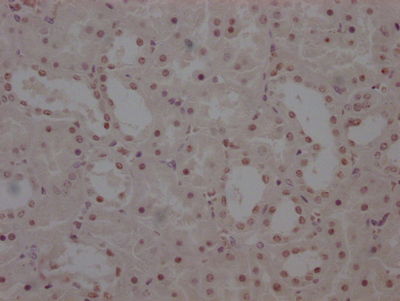

IHC image of CSB-RA555705A0HU diluted at 1:100 and staining in paraffin-embedded human skin tissue performed on a Leica BondTM system. After dewaxing and hydration, antigen retrieval was mediated by high pressure in a citrate buffer (pH 6.0). Section was blocked with 10% normal goat serum 30min at RT. Then primary antibody (1% BSA) was incubated at 4°C overnight. The primary is detected by a Goat anti-rabbit polymer IgG labeled by HRP and visualized using 0.05% DAB.